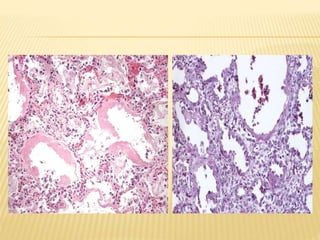

 El cuadro histopatológico en ambas

formas agudas y crónicas de

neumonitis por hipersensibilidad

incluye células mononucleares

irregulares que se infiltran en el

intersticio pulmonar, con una

característica acentuación peri-bronquial.

Los linfocitos predominan

pero las células plasmáticas y

células epitelioides también están

presentes.

 En las formas agudas de la

enfermedad, un número variable de

neutrófilos también se puede ver.

 En los casos crónicos avanzados,

la fibrosis intersticial difusa

se produce.